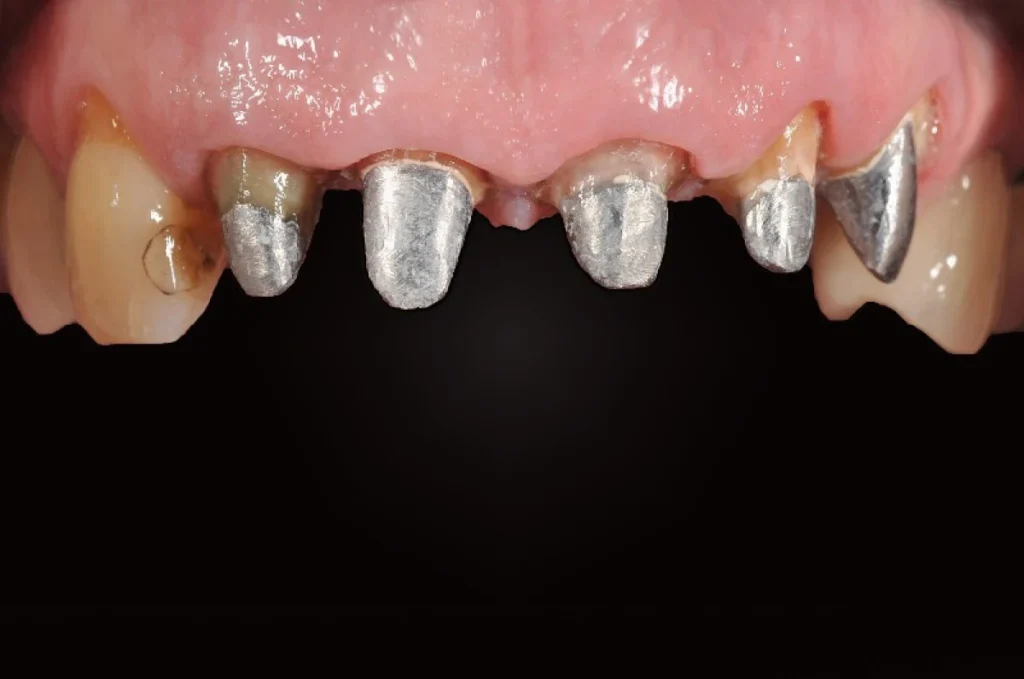

2. Les bridges dentaires fixes

Le bridge est une prothèse fixe qui permet de remplacer une ou plusieurs dents manquantes en s’appuyant sur les dents voisines. Ces dents, appelées dents piliers, servent de support pour maintenir la restauration.

Les principaux avantages du bridge sont :

- Restaurer la mastication et la fonction occlusale

- Maintenir l’équilibre de la dentition et éviter les déplacements dentaires

- Conserver l’harmonie du sourire

- Offrir une solution stable, fixe et bien tolérée par le patient

Le bridge peut être réalisé en zircone, en céramique ou en alliage métallique. Chaque choix est dicté par les besoins cliniques et les attentes esthétiques.